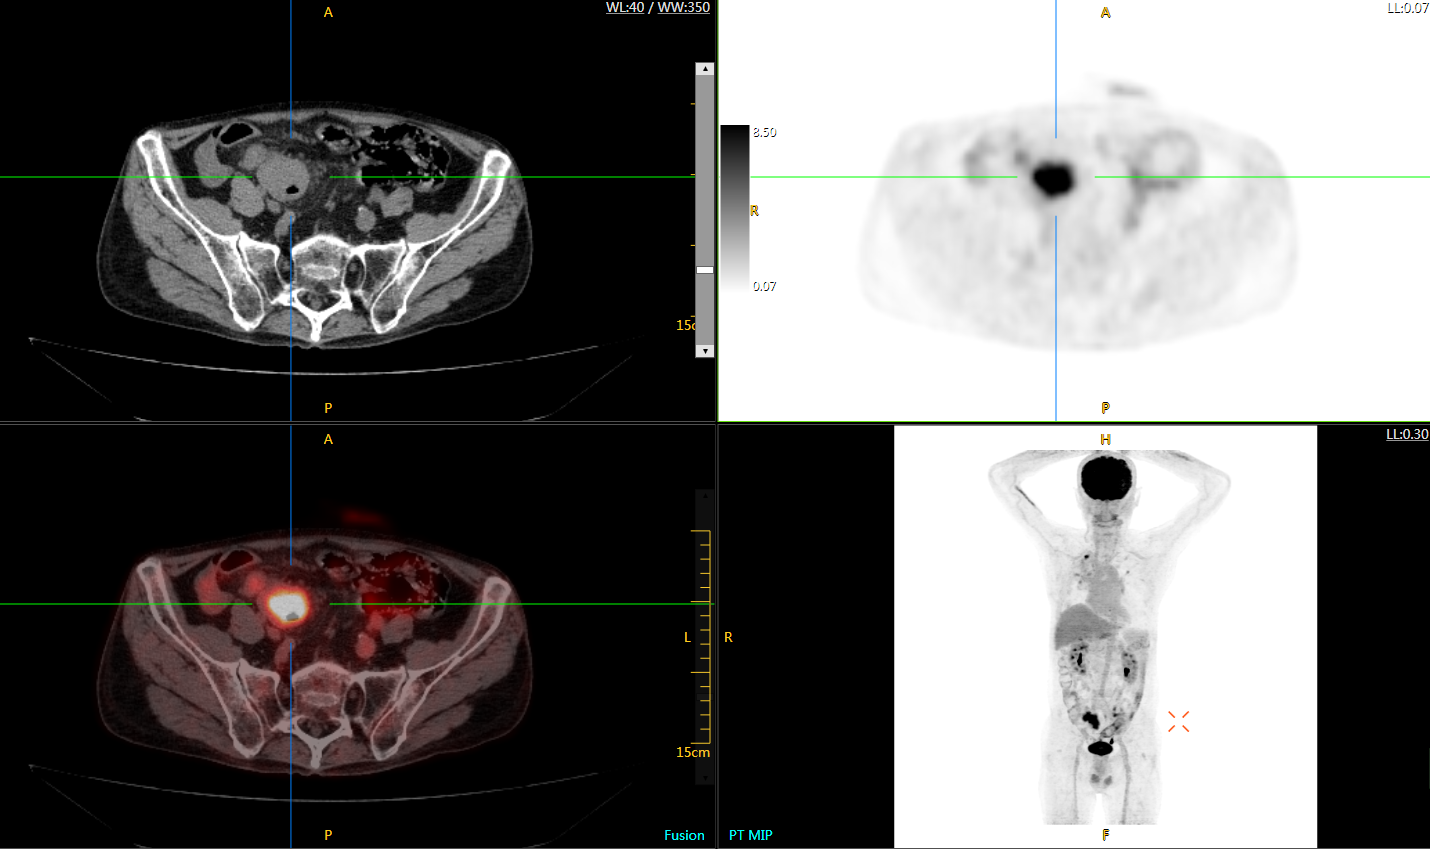

uExplorer探索者不再局限于傳統(tǒng)靜態(tài)代謝過(guò)程3D成像,而是在此基礎(chǔ)上新增一個(gè)維度——時(shí)間,從而實(shí)現(xiàn)4D全景成像。

注射總劑量為7.8mCi,14分鐘全身采集時(shí)間,在擁有超高靈敏度與超高分辨率的uEXPLORER上,即可得到展示顯示人體諸多精細(xì)結(jié)構(gòu)的高清三維圖像。

注射總劑量為7.8mCi,注射后1.6小時(shí),基于uEXPLORER探索者掃描1分鐘的圖像

注射總劑量為0.67 mCi FDG(低于常規(guī)劑量的十分之一),基于uEXPLORER探索者掃描15分鐘的圖像

注射總劑量為6.9mCi,注射后10小時(shí),基于uEXPLORER探索者掃描14分鐘的圖像